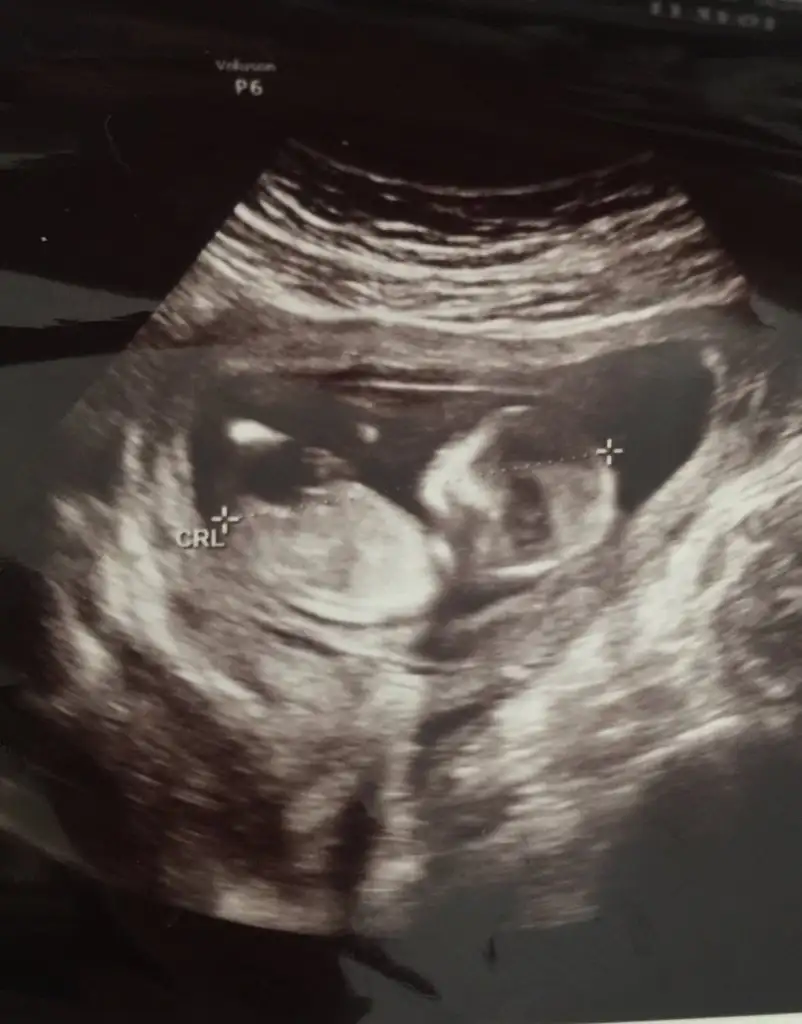

Kiz demek istedim cnm...ama tabiki tamamen his❤ saglikla gelsin

Bana erkek gibi geldi